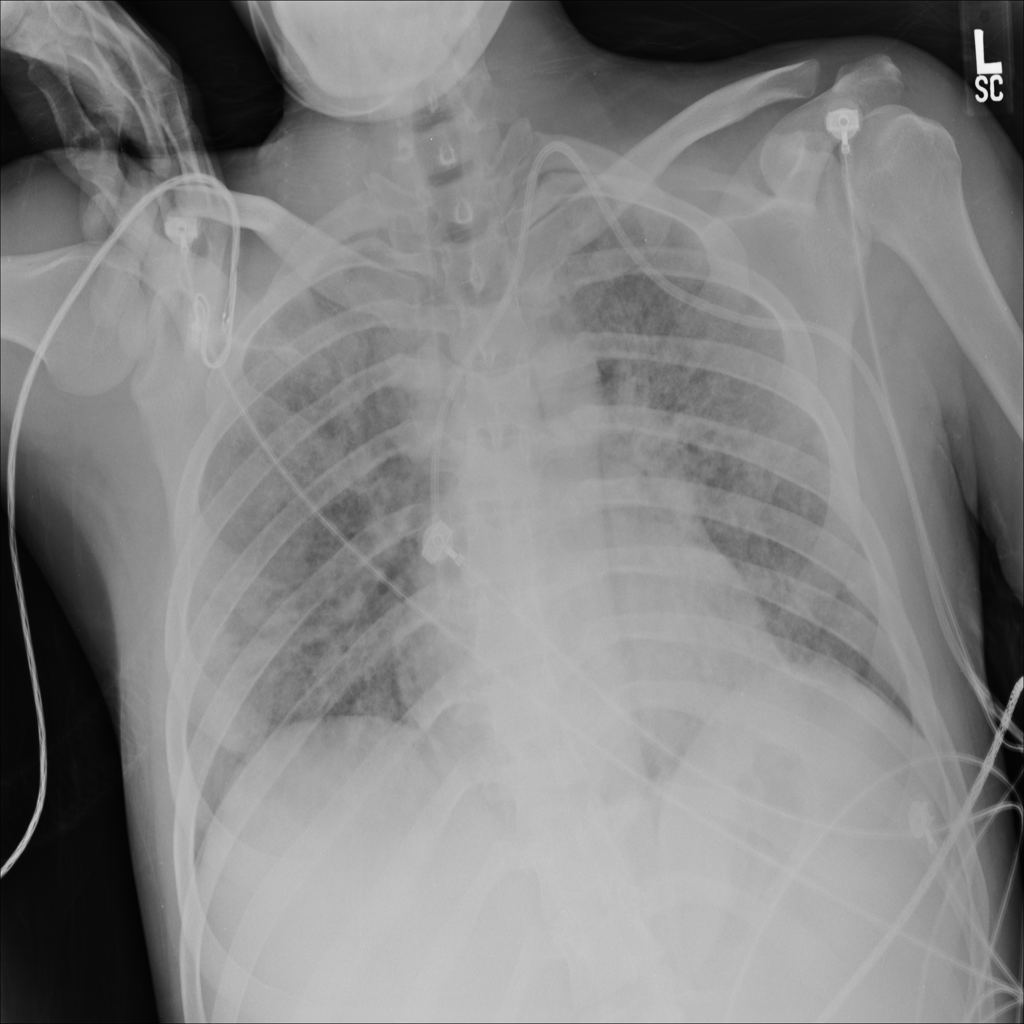

PAT-EBE1 · IMG-019Pneumonia

PAT-EBE1 · IMG-019

AP